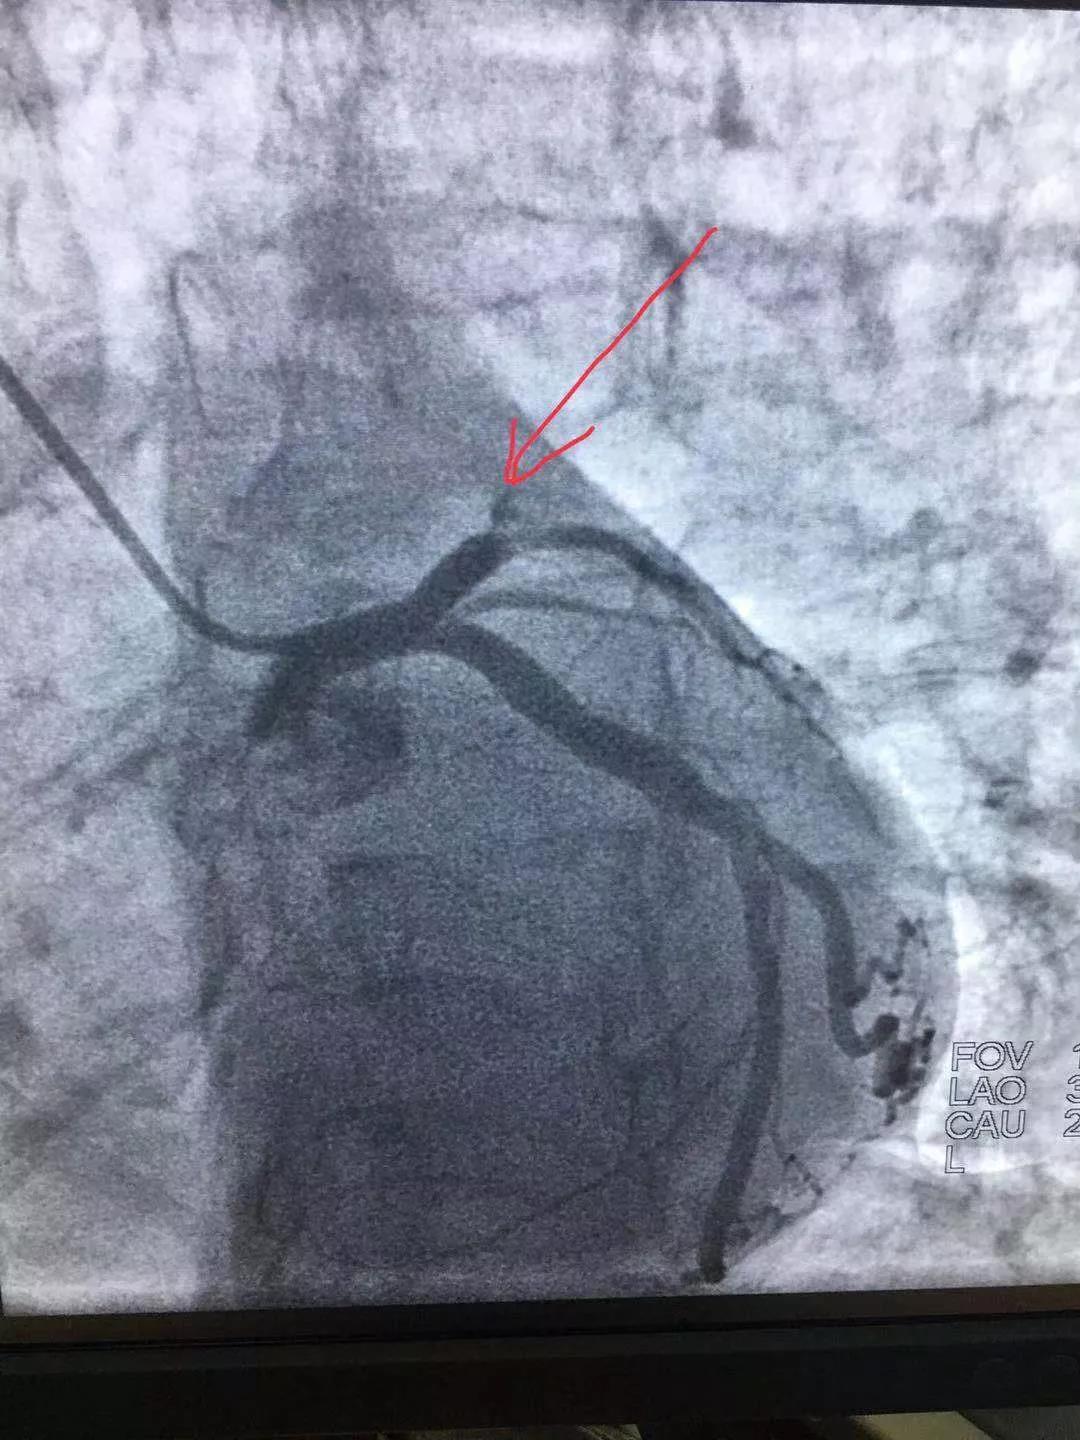

手術(shù)后與手術(shù)前

術(shù)中倫主任、徐遵敬主治醫(yī)師發(fā)現(xiàn)病人心臟前降支冠狀動脈完全閉塞,征求病人同意后馬上植入支架治療。當(dāng)冠狀動脈開通的一煞那,病人胸痛馬上消失,并在手術(shù)臺上發(fā)出了“我不痛了,我舒服了,你們真是再世華佗”的感嘆。術(shù)后病人曾出現(xiàn)頻發(fā)室性早搏,一過性左束支傳導(dǎo)阻滯,經(jīng)嚴(yán)密治療后病情好轉(zhuǎn)穩(wěn)定。